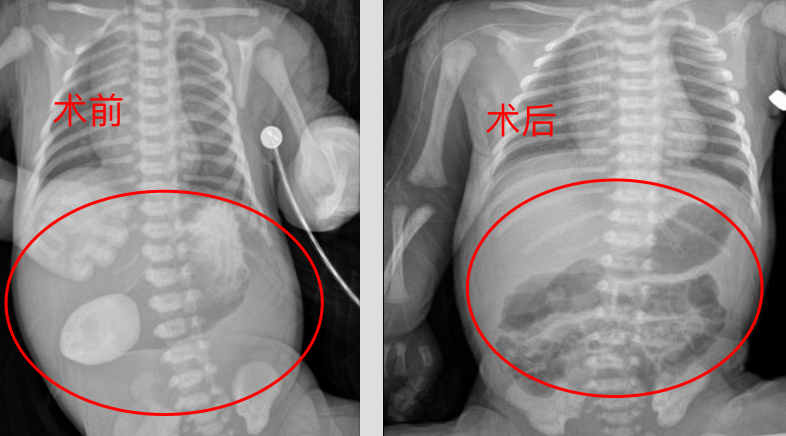

出生后,宝宝立即被送往广医三院新生儿科进一步诊治。医生检查发现,宝宝腹部平片及消化道造影均可见“双泡征”,其余腹部肠管未见充气,确认是先天十二指肠梗阻。

患儿术前(左)和术后(右)腹平片对比图:左图显示术前消化道造影可见“双泡征”,右图可见其远端肠管充气,肠梗阻解除。